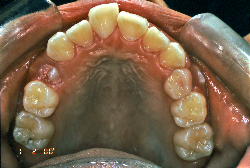

「ものがうまく噛めない」という主訴で来院したケースです。診断の結果、「骨格性反対咬合に伴う咬合不良+軽度叢生」と判明しました。原因としては特に下顎の左側が過成長したため、骨格性反対咬合になり、特に左側での噛み合わせが非常に悪くなっていると診断しました。初診時の写真を見ると、上下の正中線の大きなズレ、左側の噛み合わせの不良がはっきり分かります(黄色の矢印と緑の矢印は一致しているのが正しい状態です)。